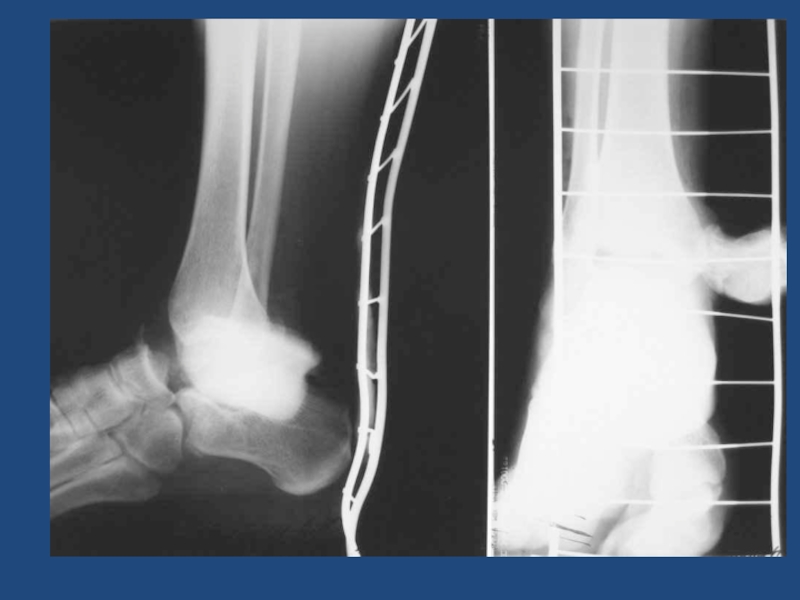

Слайд 5554

Срастающийся перелом с/3(н/3)б/б кости. (ложный сустав)Центромедулярный блокирующий остеосинтез

54Срастающийся перелом с/3(н/3)б/б кости. (ложный сустав)Центромедулярный блокирующий остеосинтез